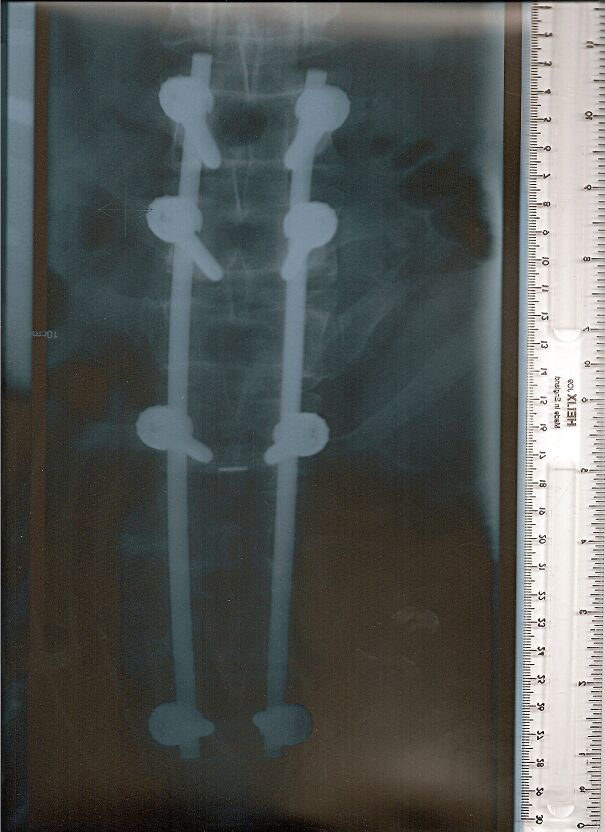

An X-ray showing Robbie Knievel’s spine and an actual photograph of the metal device after he passed away in January 2023.